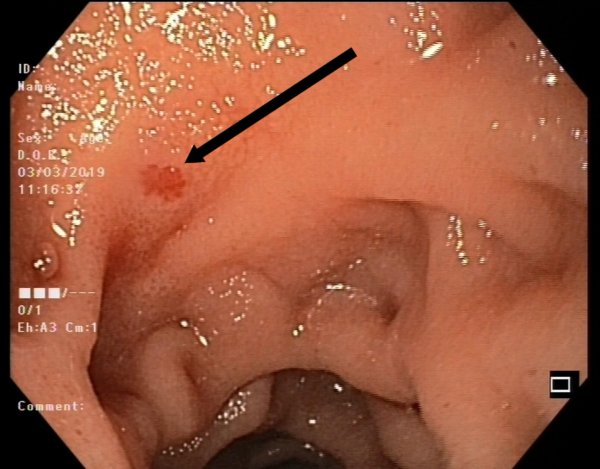

ظاهر مخاط معده در اندوسکوپی سالم

مخاط معده سالم صاف، یکنواخت و با رنگ صورتی روشن است. رگهای خونی مشخص و بدون تغییرات غیرطبیعی دیده میشوند. لایه مخاطی سالم بدون زخم، توده یا التهاب شدید است و حرکات طبیعی معده هنگام عبور آندوسکوپ مشاهده میشود.

تغییرات اولیه سرطان معده

در مراحل اولیه، سرطان معده ممکن است تغییرات ظریف ایجاد کند که نیاز به دقت بالای پزشک دارد:

-

نواحی قرمز یا تیره غیرمعمول در مخاط معده

ضخیم شدن موضعی یا برآمدگیهای کوچک

زخمهای سطحی با حاشیه نامنظم

تغییرات رنگ و بافت مخاط نسبت به مناطق اطراف

این تغییرات معمولاً کوچک هستند و بدون بیوپسی، تشخیص قطعی سرطان دشوار است.